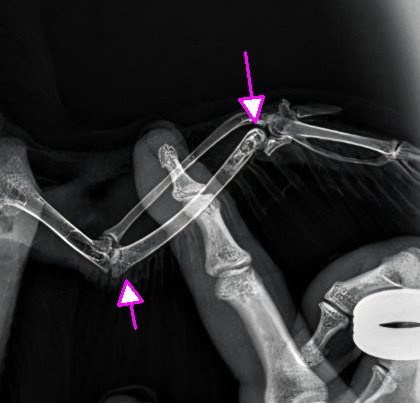

14. Zekai

3. Странно, на рентгене что-то видно именно на левом. Но да, тут лучше к Зосе.